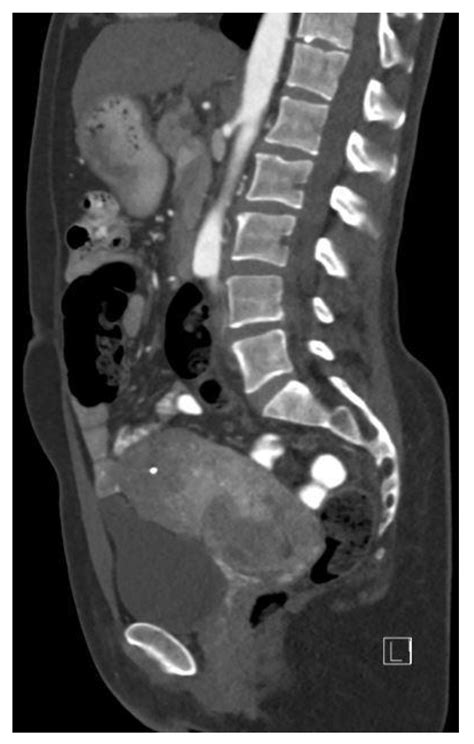

Imaging studies such as computed tomography (CT) scans, magnetic resonance imaging (MRI), and positron emission tomography (PET) scans are often used to visualize the tumor and assess its extent. These imaging techniques can help identify the location and size of the tumor, as well as any metastases.